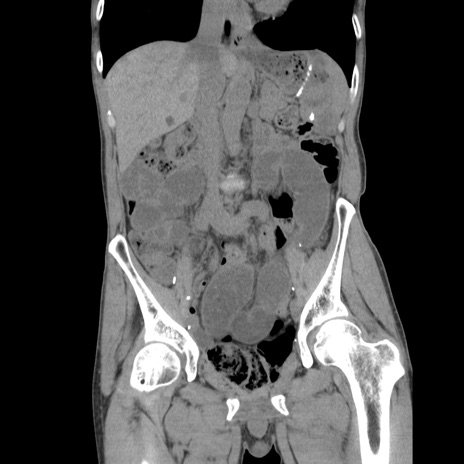

症例11(冠状断像)

【症例】 60歳代男性

【主訴】 下腹部痛

【現病歴】 本日夜中より下腹部痛の症状認め、受診。

【既往歴】 膀胱癌(膀胱全摘+尿管皮膚瘻術) 、胃癌術後

【身体所見】 BT 35.3℃、PR 58/min、BP 136/98mHg、腹部平坦、軟、腸蠕動音±、ストマ留置あり、左上腹部~正中部に圧痛あり、反跳痛なし。

【データ】WBC 5100、CRP0.01